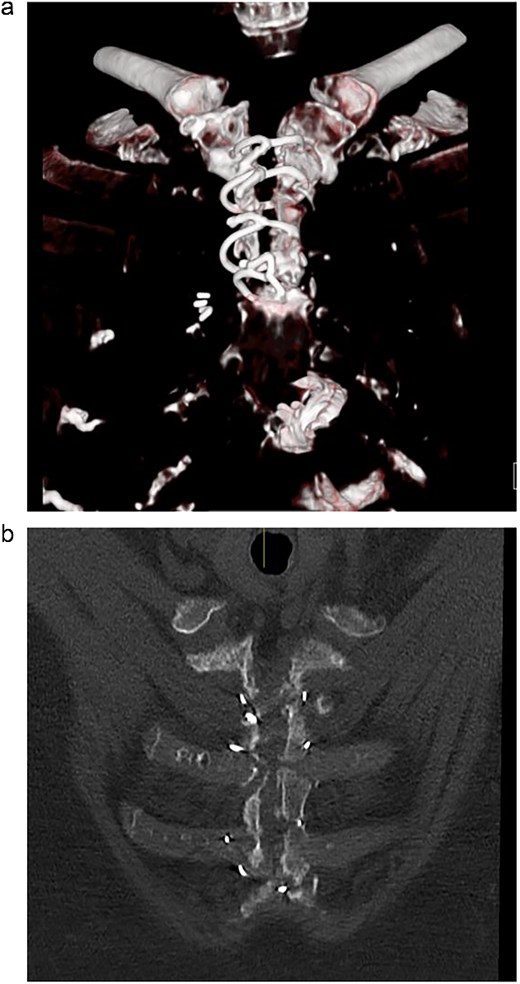

A computed tomography (CT) of the sternum revealed distracted upper sternal edges by 5-11 mm (Fig. 1a). The right upper hemi-sternum had multiple fractures with significant bone loss (Fig. 1b). Her lung fields were clear and baseline bloods were normal. She was diagnosed with sterile mechanical SD and planned for elective rigid sternal fixation.

(a) Pre-operative CT scan showing dehisced upper hemi-sternum. (b) Pre-operative CT showing significant bony loss on the right hemi-sternum.